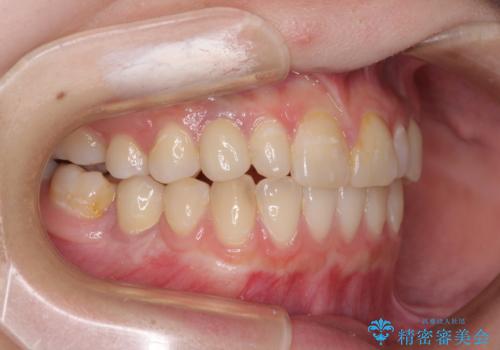

欠損と残存乳歯 矯正治療とインプラント治療

- 残存した乳歯や歯の欠損、歯並びを気にして来院された患者様です。

乳歯を残した状態は予後がよくないこと、矯正治療と補綴治療を総合的に進めていきたいとのことで、インビザラインによる矯正治療とインプラント補綴治療を並行して進めていくこととしました。

当院は矯正治療もインプラント補綴治療も、同一の歯科医師が担当するため、矯正治療を行いながら、最適なタイミングでインプラント補綴治療を行うことが可能です。

気になっていた部分がすべて解消され、患者様には大変満足していただきました。